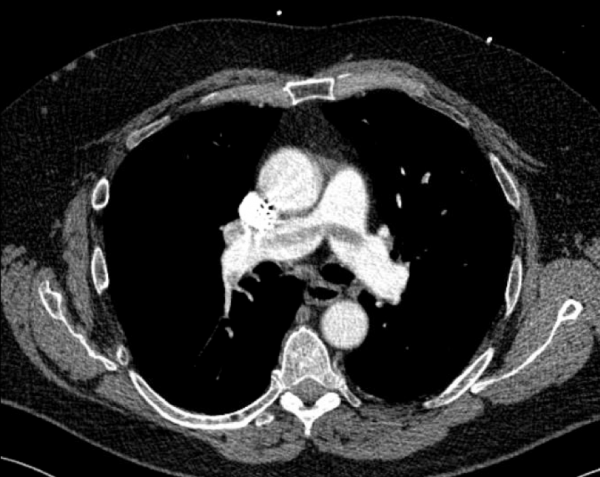

CT angiography of the chest with intravenous contrast was performed.

There is a filling defect straddling the bifurcation of the pulmonary trunk extending into the distal branches of the right lower, right middle, right upper and left upper lobe consistent with a saddle embolism. Bedside echocardiography revealed mild concentric hypertrophy, an ejection fraction of 60%, with normal right ventricular global systolic function, with no evidence for an elevated right ventricular systolic pressure.